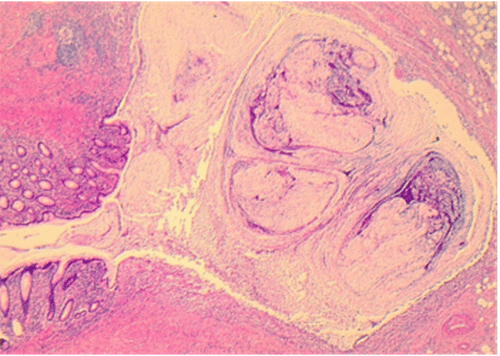

Intraoperatively, the appendix was found to be markedly dilated, firm, and adherent to the retroperitoneum at the sacrum (Figure 3). Both caecum and appendiceal base were thought to be unremarkable, with no concerning features of malignancy seen elsewhere in the abdomen. Given the dilated appendix, we performed a laparoscopic appendicectomy with partial caecectomy (Figure 4). A portion of the caecum attached to the appendiceal base was resected to allow for a greater margin due to the suspicion that the appearance of the appendix may indicate a neoplasm.

Figure 3. Intraoperative Photo at Laparoscopy Demonstrating Dilated and Firm Appendix (*) Adherent to Retroperitoneum (#). Published with Permission